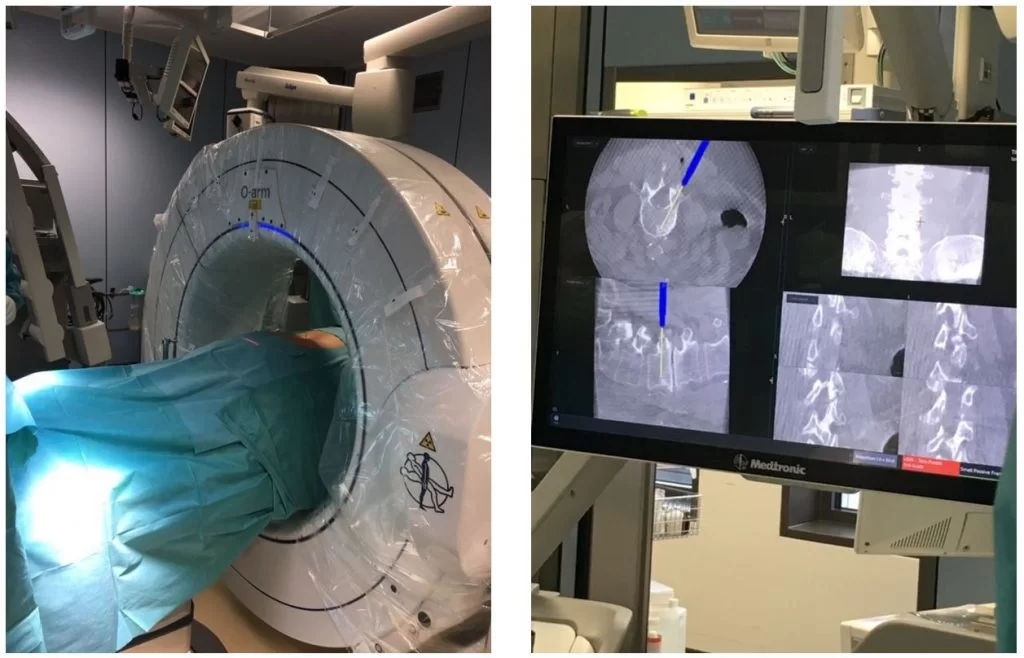

Οι σύγχρονες τεχνικές και η τεχνολογία επιτρέπουν πλέον η σπονδυλοδεσία να πραγματοποιείται με πολύ μικρές τομές και ελάχιστο τραύμα (και κατ’ επέκταση πόνο) για τον ασθενή. Η πιο σύγχρονη μέθοδος είναι η διαδερμική σπονδυλοδεσία με νευροπλοηγό (Εικόνες 4 – 6). Στην τεχνική αυτή, οι βίδες και οι ράβδοι τοποθετούνται μέσα από πολύ μικρές τομές και με τη βοήθεια της 3D-νευροπλοήγησης τα μοσχεύματα μπορούν να τοποθετηθούν με εξαιρετική ακρίβεια.